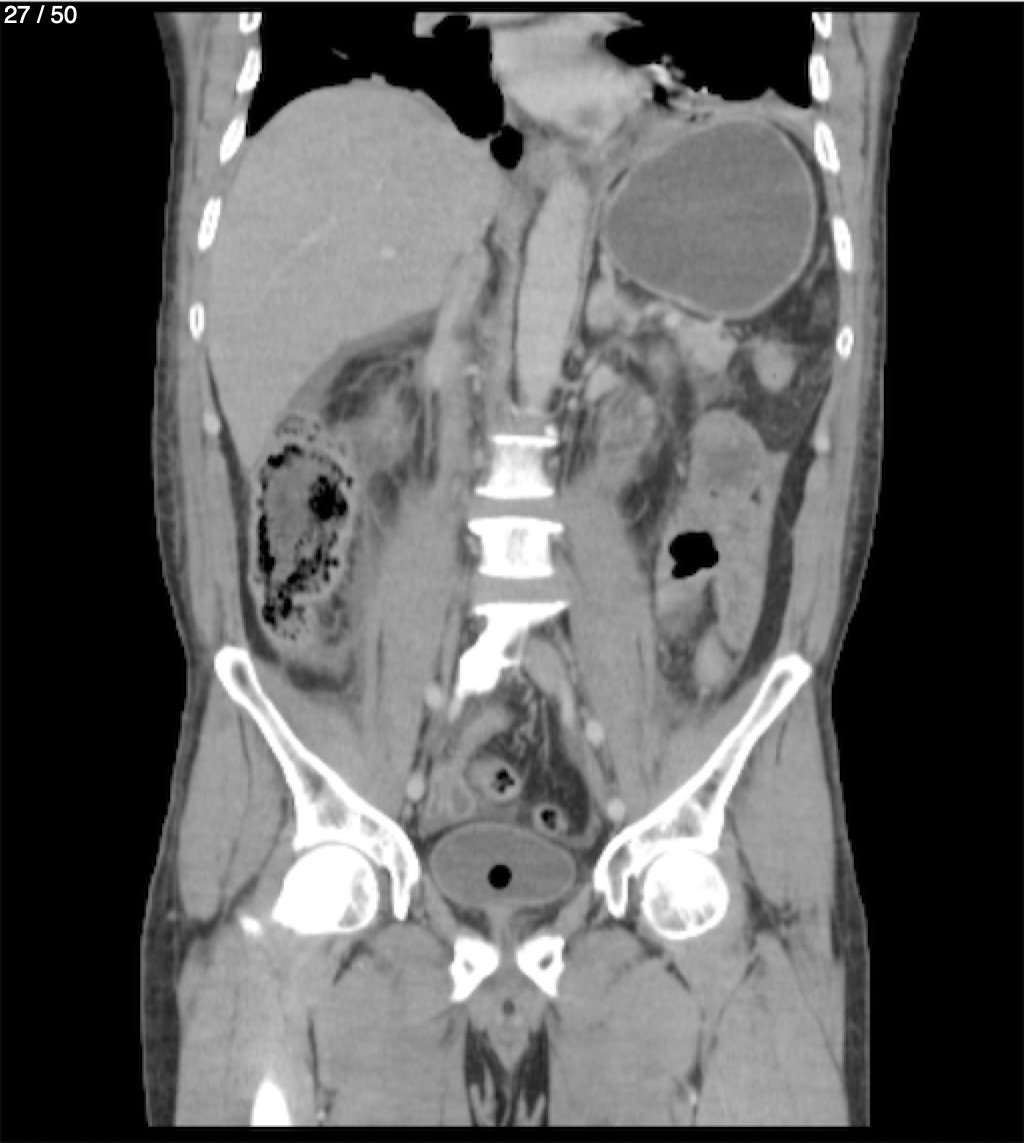

Alonso Victorio Ruiz 62A - T.C Abdomen Syc